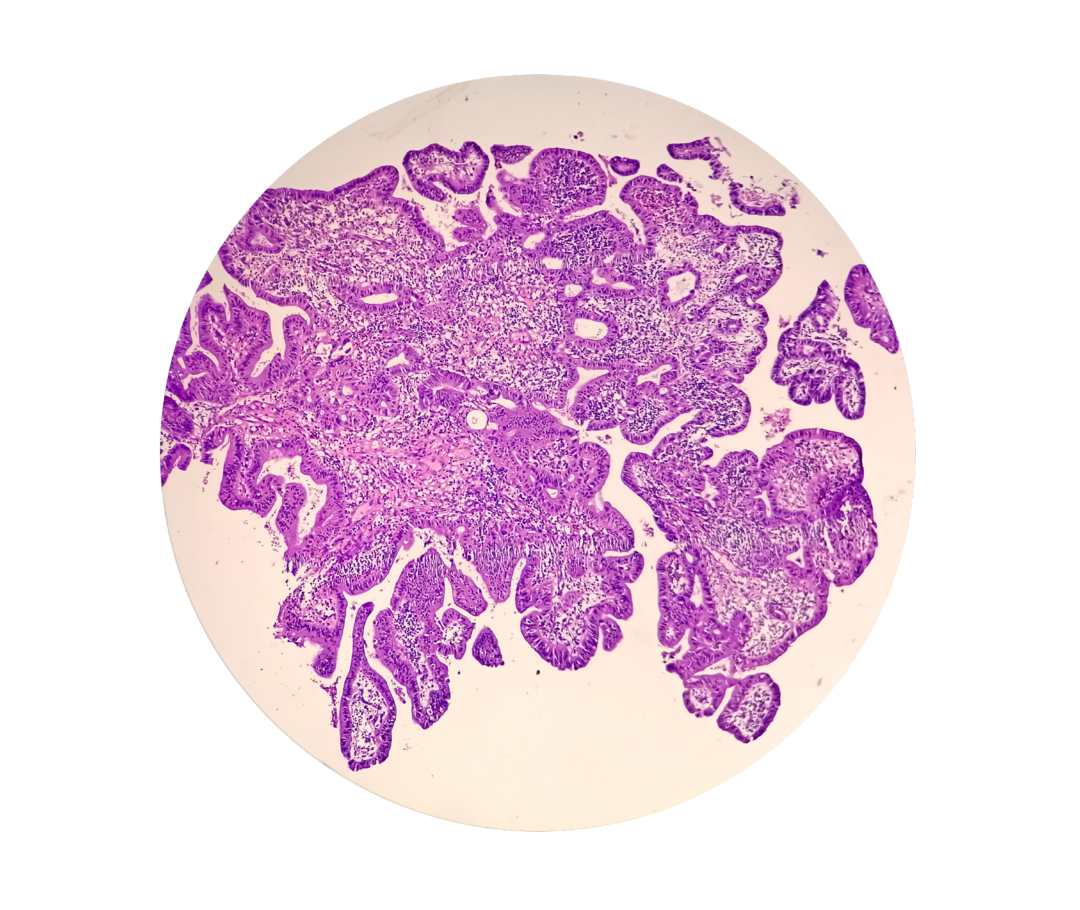

Es ist ein histologischer Schnitt von Prostatakrebsgewebe zu sehen.

Abb. 1 Mikroskopisches Bild von Prostatakrebsgewebe.

Die Aggressivität der Prostatakrebszellen wird daran gemessen, wie stark sie sich von den Ursprungszellen in der gesunden Prostata unterscheiden. Sehen sie den natürlichen Prostatazellen noch sehr ähnlich, stuft man die Erkrankung als wenig aggressiv ein, das heißt, der Tumor wächst vermutlich eher langsam und bildet weniger wahrscheinlich Metastasen. Die Bewertungsskala für die Aggressivität ist der Gleason-Score (Tabelle). Dafür bestimmt der*die Patholog*in das am häufigsten vorkommende sowie das aggressivste Wachstumsmuster (siehe Abb. 2) der Krebszellen in der Biopsie. Diese beiden Werte werden zum Gleason-Score zusammengerechnet. Der Gleason-Score spielt außerdem eine wichtige Rolle für die Behandlungsplanung.2,3